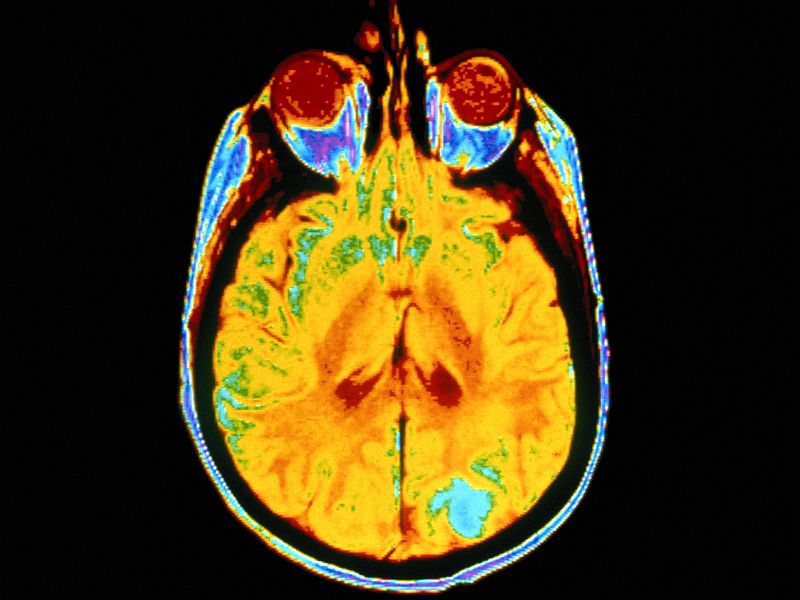

The participants then underwent brain scans while performing a decision-making task known to engage parts of the brain affected by nicotine.

The thalamus -- an important binding site for nicotine in the brain -- showed a dose-dependent response to each person’s beliefs about the nicotine strength of their e-cigarette.

A similar effect also was observed in the connectivity between the thalamus and the ventromedial prefrontal cortex, a brain region that is considered important for decision-making and belief states.